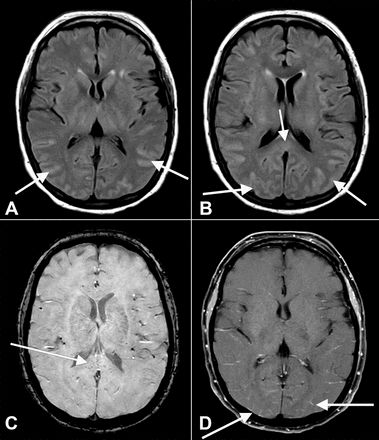

根据密歇根大学密歇根医学部的一项新研究,一些发生严重感染导致住院的COVID-19患者(包括在重症监护室的患者),可能会出现长期谵妄。这项研究涉及大约150名在大流行病早期因COVID-19而住院的人,其中大多数人最终出现了谵妄。

谵妄是一种认知问题,在这种情况下,某人能够不能清楚地思考,经常经历激动和混乱。这个问题可能由多种原因导致,包括可能在COVID-19感染期间经历的脑部炎症。在这项研究中使用的150名左右的病人中,73%的人最终出现谵妄症状。

该研究发现,出现谵妄的COVID-19患者更有可能有糖尿病等合并症,而且他们往往比其他患者病情更重。研究人员指出,在SARS-CoV-2和由此产生的疾病中,多种因素可能导致谵妄的发生,包括血栓、中风、缺乏足够的氧气和大脑炎症。

不幸的是,一些用于帮助减少谵妄的方法并不适合许多COVID-19患者,例如允许他们接受访客或家中的个人物品。使问题复杂化的可能是在严重的COVID-19病例中通常使用的镇静剂,特别是那些最终在ICU中使用呼吸机的人。

研究发现大约三分之一参与研究的人在出院时仍有谵妄症状;在这些病人中,40%的人在离开医院后需要专业护理。在某些情况下,病人在感染后的几个月内仍然出现谵妄,这使其成为该大流行病的多种长期潜在后果之一。